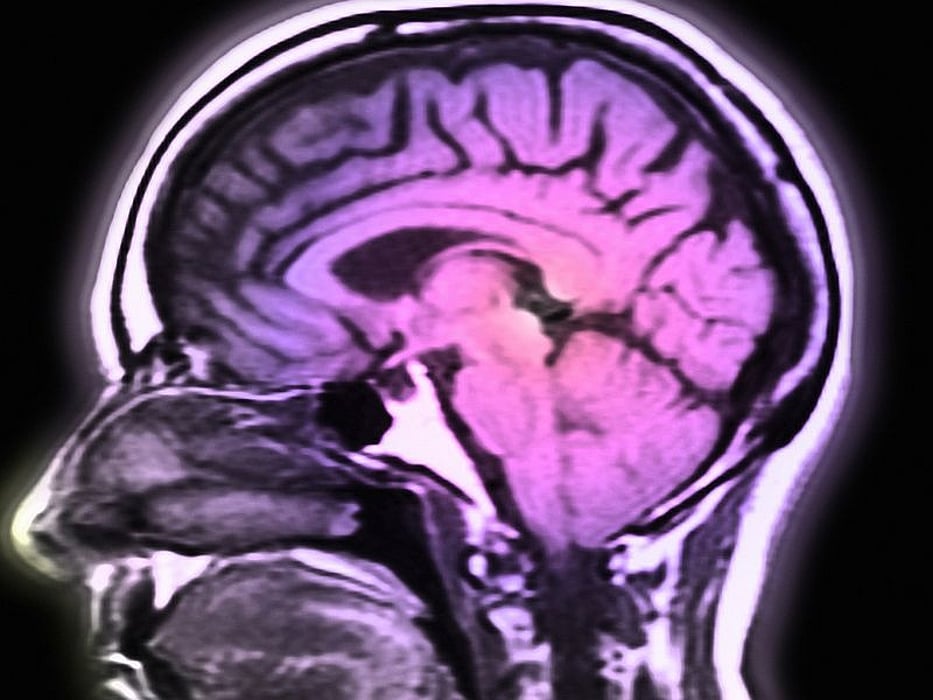

脳卒中 画像診断 遠隔-脳画像の視方のポイント v障害部位別の症状 viまとめ 画像診断の目的 ヨネシソチビが治療を進める上での画像情報 の有用性。 ①損傷機序,損傷部位の把握 ②ヨシキの把握 ③機能障害の予測 ④予後予測 脳卒中の画像検査 CT 明らかな脳卒中症状 画像診断3/07/14 · 脳卒中に適した画像はctなのでしょうか?それともmriなのでしょうか? mriは脳梗塞に強いと言われますが、実際の所どうなのでしょうか? 脳卒中に適した画像についてまとめてみました。 脳卒中に適した画像の撮影モダリティと

脳卒中リハビリテーション看護認定看護師 プログラム 1.脳卒中のケアにはまずは脳画像から ~画像の見方にはコツがある。どこを見るかポイントを押さえる~ 2.脳に関連するバイタルサインの捉え方 ~そのバイタルサインが脳にどんな影響を与えて脳卒中の診断 症状の確認とmri等の画像診断を行う 脳卒中の診断では、まず、診察によって脳卒中による症状が現れていないか確認していきます。 その後、ctやmri等の画像診断を行います。18/09/ · みなさま、はじめまして 見て頂いてありがとうございます🙇 今回は ワレンベルグ症候群と脳画像 についてまとめていきたいなと思います。 ※できるだけ正しい情報の発信に努めていますが、あくまで個人のまとめ、私の臨床経験や考えも含みますので、より正確な情報を知りたい方は、原

脳回・脳溝の名称を理解する際には,大脳の側面 像が有用である。前頭葉や側頭葉では前後方向に走 セミナーⅠ:脳画像 脳画像の読み方:基礎編 石 原 健 司* 要旨:脳画像は診断のみならずリハビリテーションでも有用な情報を提供してくれる。中脳レベルの脳画像と、損傷部位から予測される高次脳機能障害! 19年4月22日 脳卒中 脳画像 脳画像を観れるということは、脳画像上の傷部位からどのような症状が生じるかを予測できるというこ脳力①もう怖くない!脳画像 押さえておきたい脳画像のポイント 見えない脳が見える 複雑な脳血管の走行と 機能が簡単に理解できる 脳力②看護師目線の脳卒中 ~病態と必要な看護のつながりを学ぼう 脳梗塞はどれも同じ?

脳卒中発症後には、脳出血にしろ、脳梗塞にしろまずは脳の状態を少しでも早く知るために脳画像でも ct画像をとります。 これは MRIでは撮影時間が長く 、場合によっては適切な処置を遅らせてしまう原因に繋がるからです。専門外来のご案内 脳卒中外来 物忘れ外来 脳卒中の種類 脳卒中の予防 物忘れの種類 脳卒中外来 激しい頭痛、吐き気、めまい、ふらつき、手や足の感覚異常、物が二重に見える、言葉がもつれる、力が入りにくいなどの症状の場合に受診していただいています。3.脳卒中患者における画像プロトコール 脳卒中患者の治療は時間との勝負でありいかに的確に 短時間に診断することができるかがポイントとなる。脳 卒中患者の診断に必要と思われる情報を表にまと